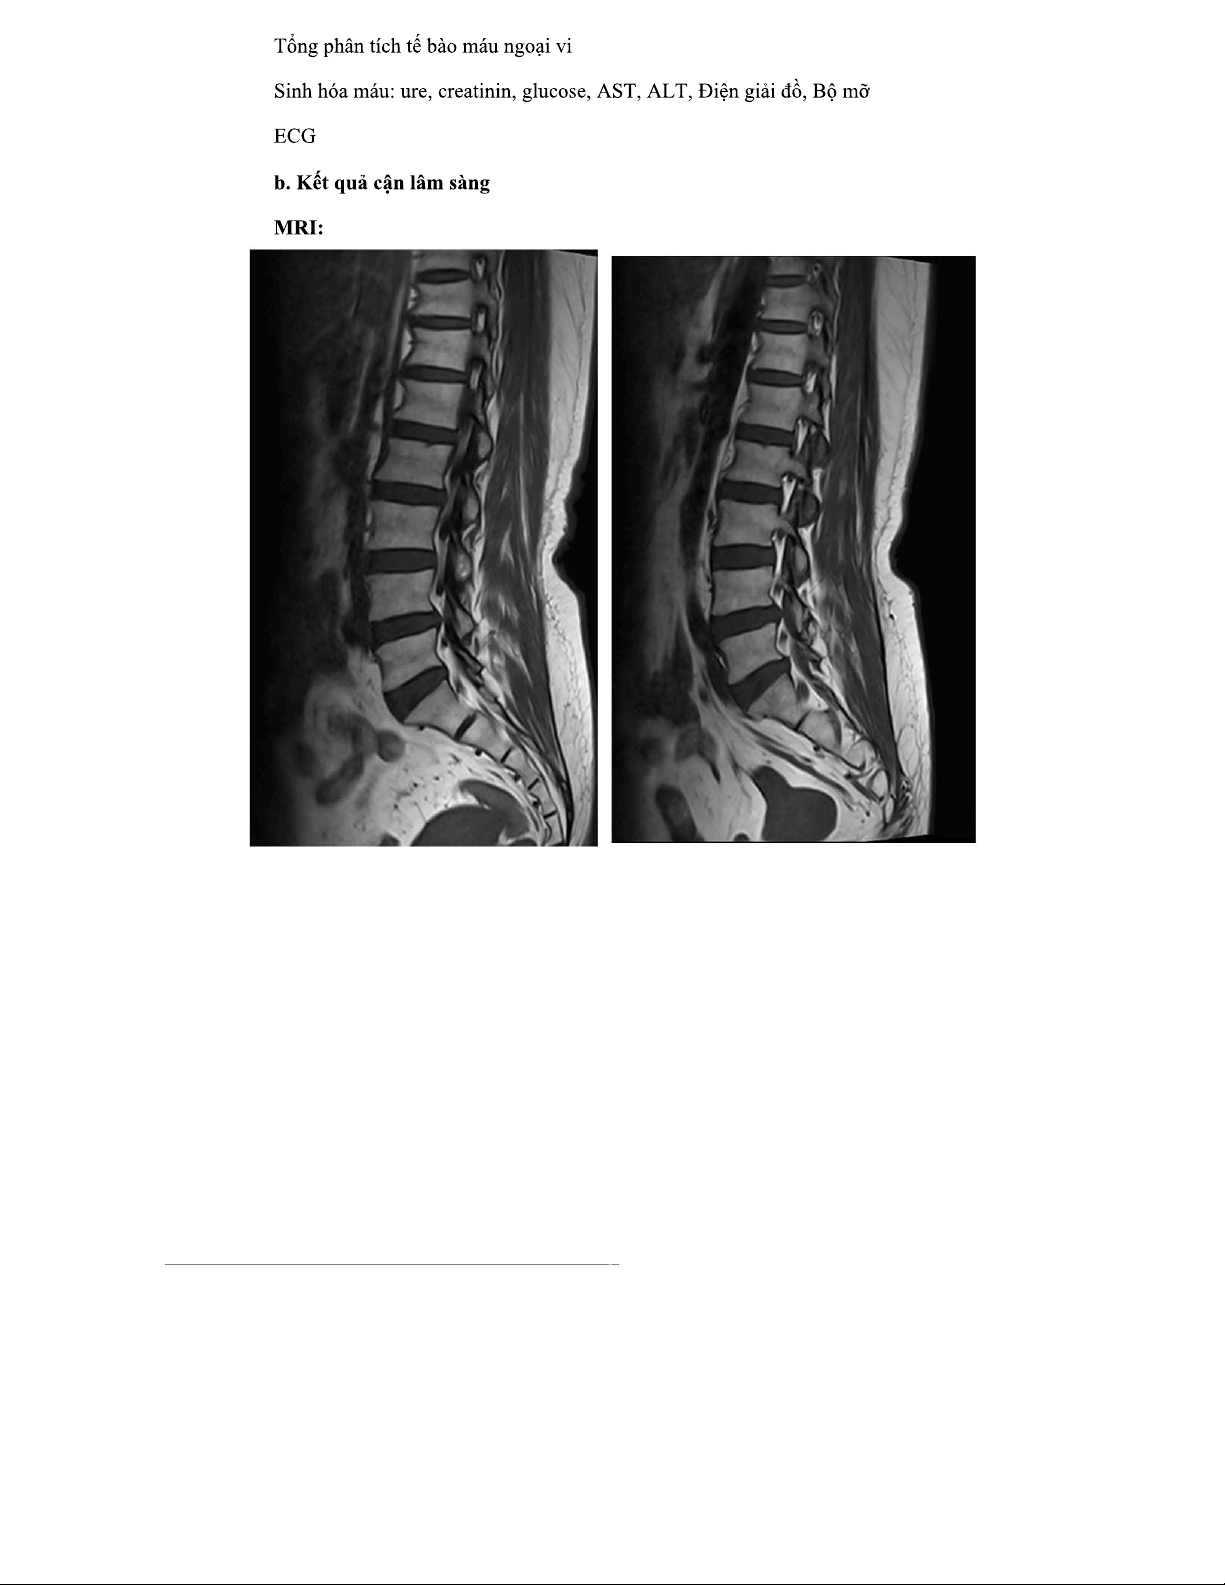

BỆNH ÁN NGOẠI THẦN KINH - Thoát Vị Đĩa Đệm L4/L5, L5/S1